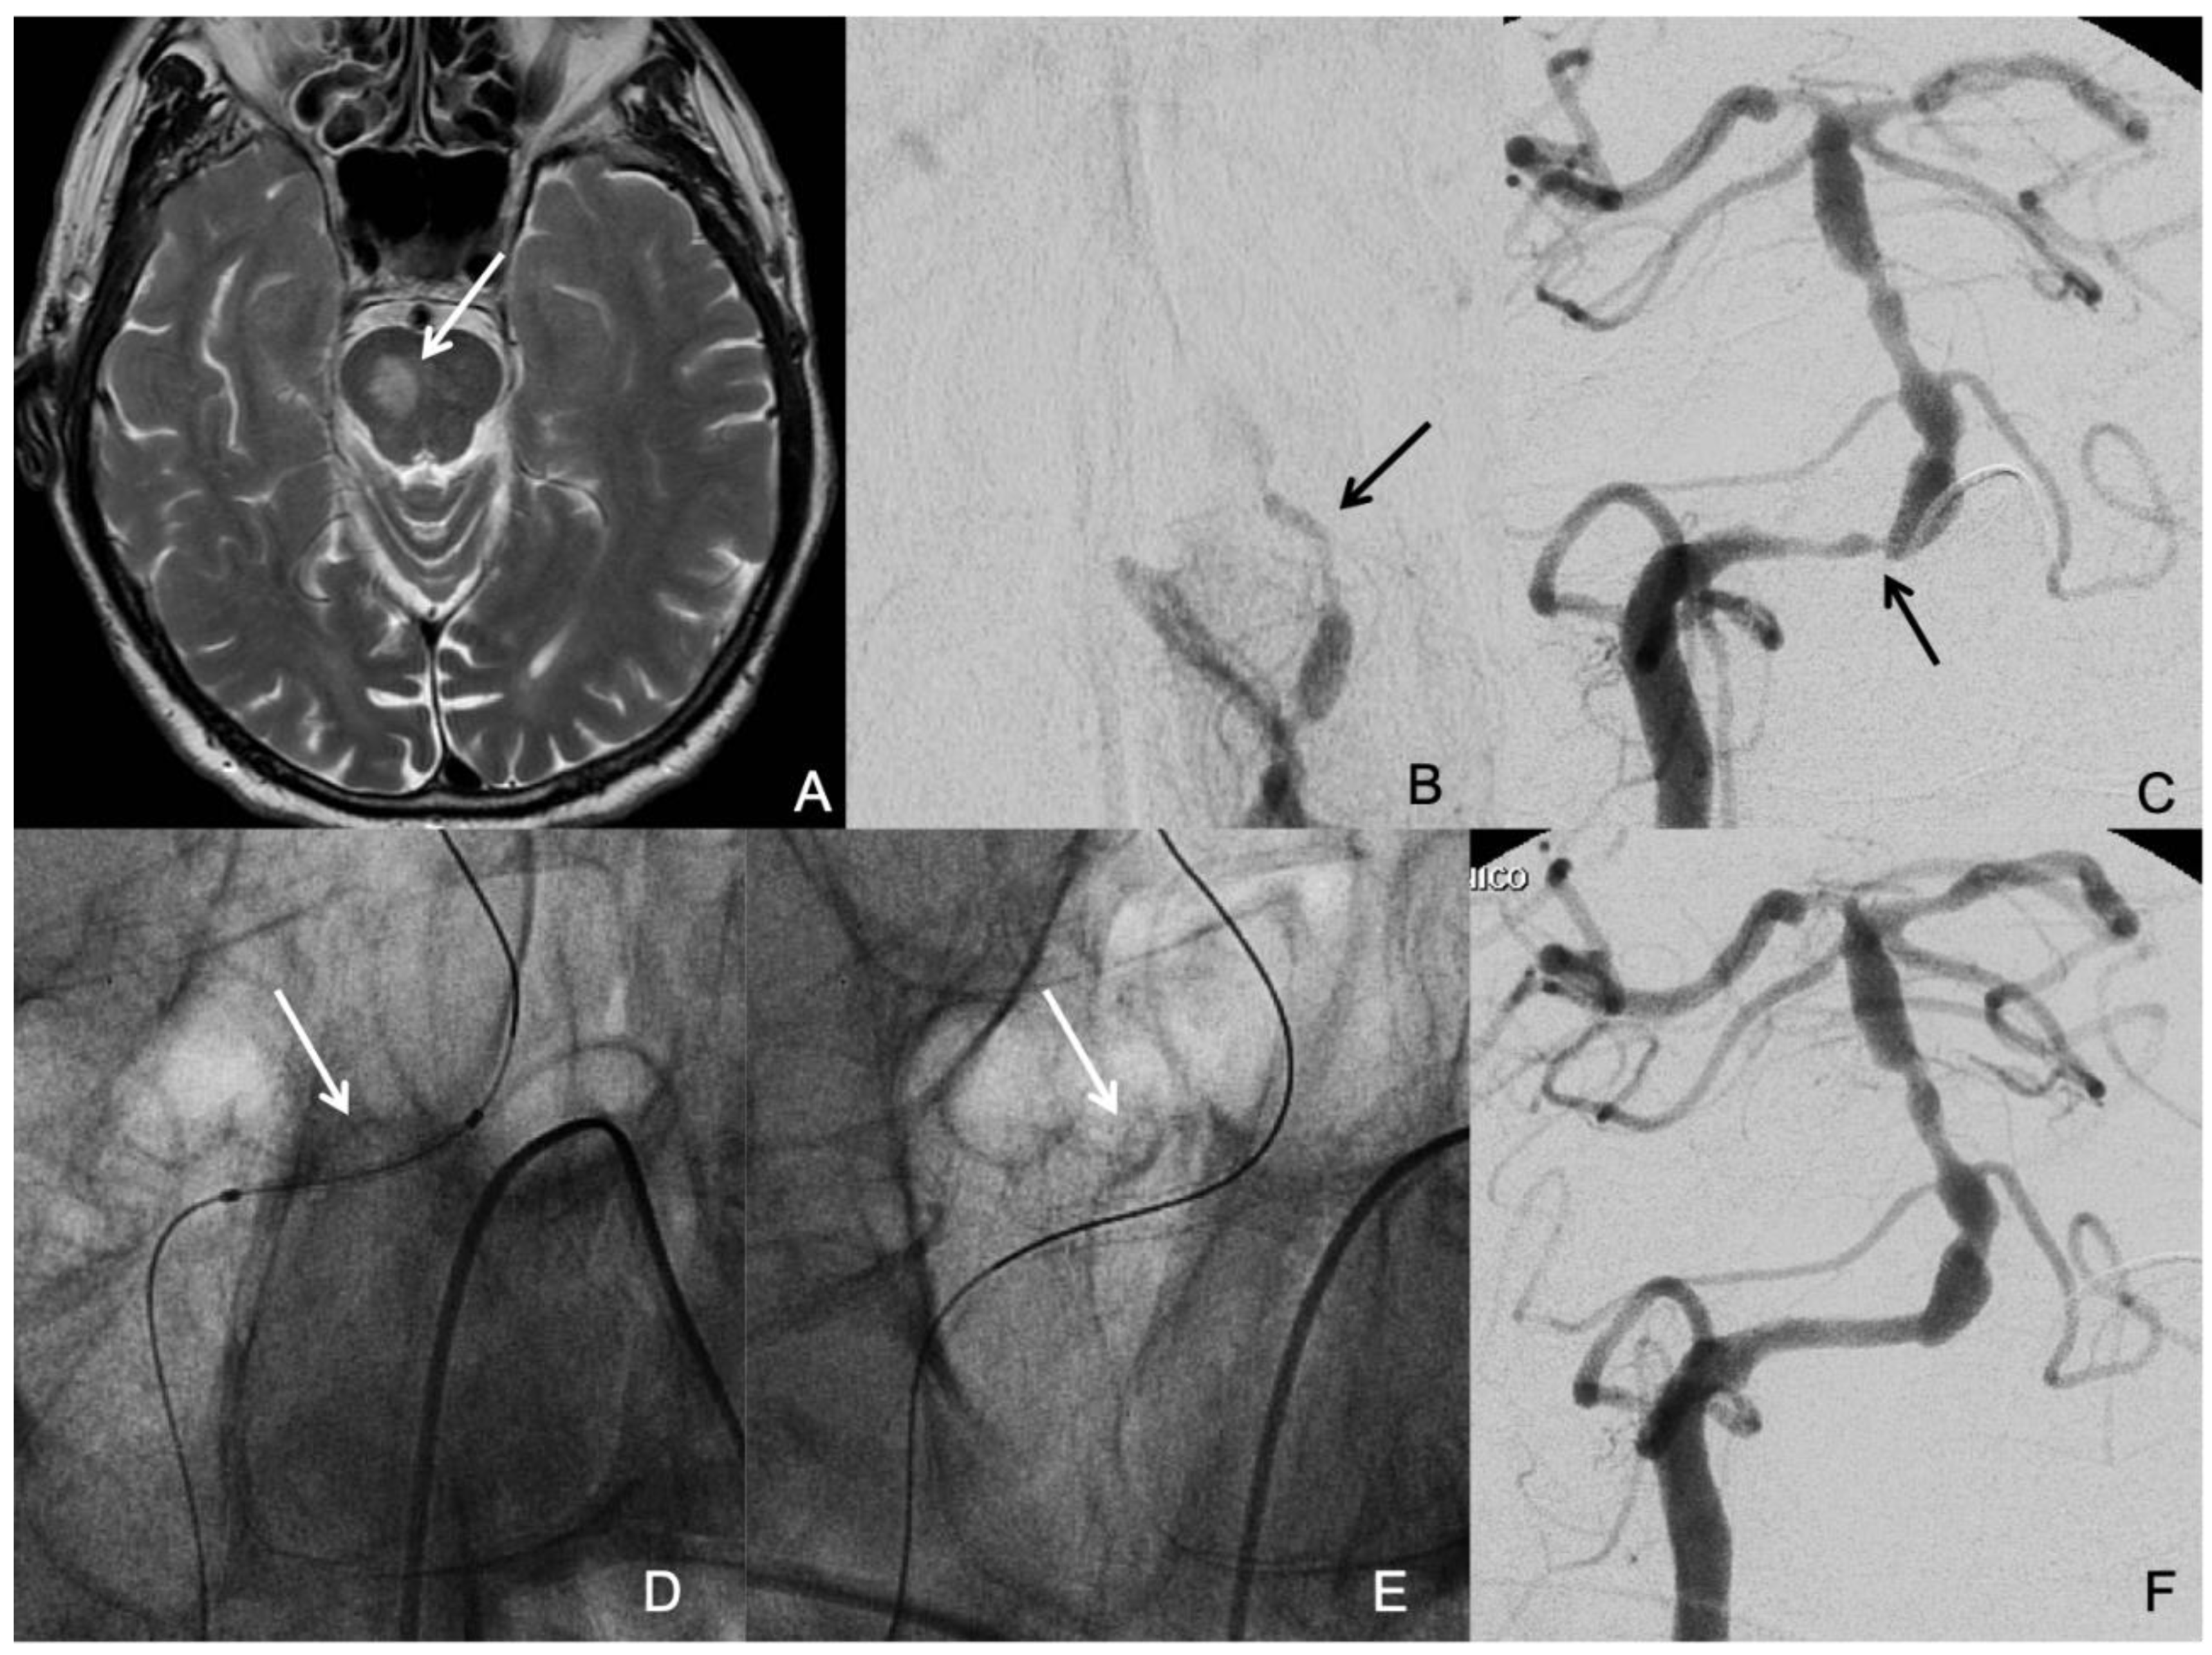

The symptomatic qualifying artery was basilar artery in 15 patients (41.7%), intracranial vertebral artery in 13 patients (36.1%), middle cerebral artery in 3 patients (8.3%), and intracranial internal carotid artery in 5 patients (13.9%). The mean degree of stenosis was 86.6 % ± 8.7 SD. The mean lesion length was 7.34 mm ± 3.2 SD. The time from the qualifying event to intervention ranged from 2-78 days, with a mean time of 24.6 days ± 21.9 SD, and a median time of 17 days. The most likely stroke mechanisms related to ICAD were mixed mechanisms in 47.2% (17/36), hypoperfusion in 27.8% (10/36), and artery-to-artery embolism in 25% (9/36). Neither perforator occlusion nor insitu thrombotic occlusion was present as the sole stroke mechanism in any patient of our study population. Thirteen patients (36.1%) had multiple significant ICAD (Figure 1). Five patients (13.9%) had concomitant significant Extracranial Atherosclerotic Disease (ECAD). Two patients (5.6%) had significant stenosis (≥70%) proximal to the target lesion i.e. tandem stenosis. Twenty-one patients (58.3%) had tortuous proximal vessels (≥ 2 acute curves).

Figure 1. A patient who suffered a right medial pontine infarction (arrow in A) and had several drop attacks due to hypoperfusion secondary to occlusion of the left vertebral artery (arrow in B) and severe stenosis of the right vertebral artery at the vertebra-basilar junction (arrow in C). An undersized coronary balloon expandable stent was placed in the right vertebral artery at the site of the stenosis (arrows in D and E) with good resolution of the stenosis.